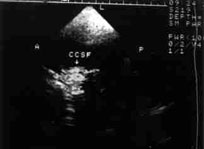

脑多普勒超声(TCD)是通过脑多普勒超声对脑进行检查的一种方法,经颅彩色多普勒显象:经颞窗、枕窗、眶窗探查,可探及大脑动脉,根据颅内血管的流速、频宽、流向异常或音频异常等确定,应用于脑血管疾病的诊断及病因分类。